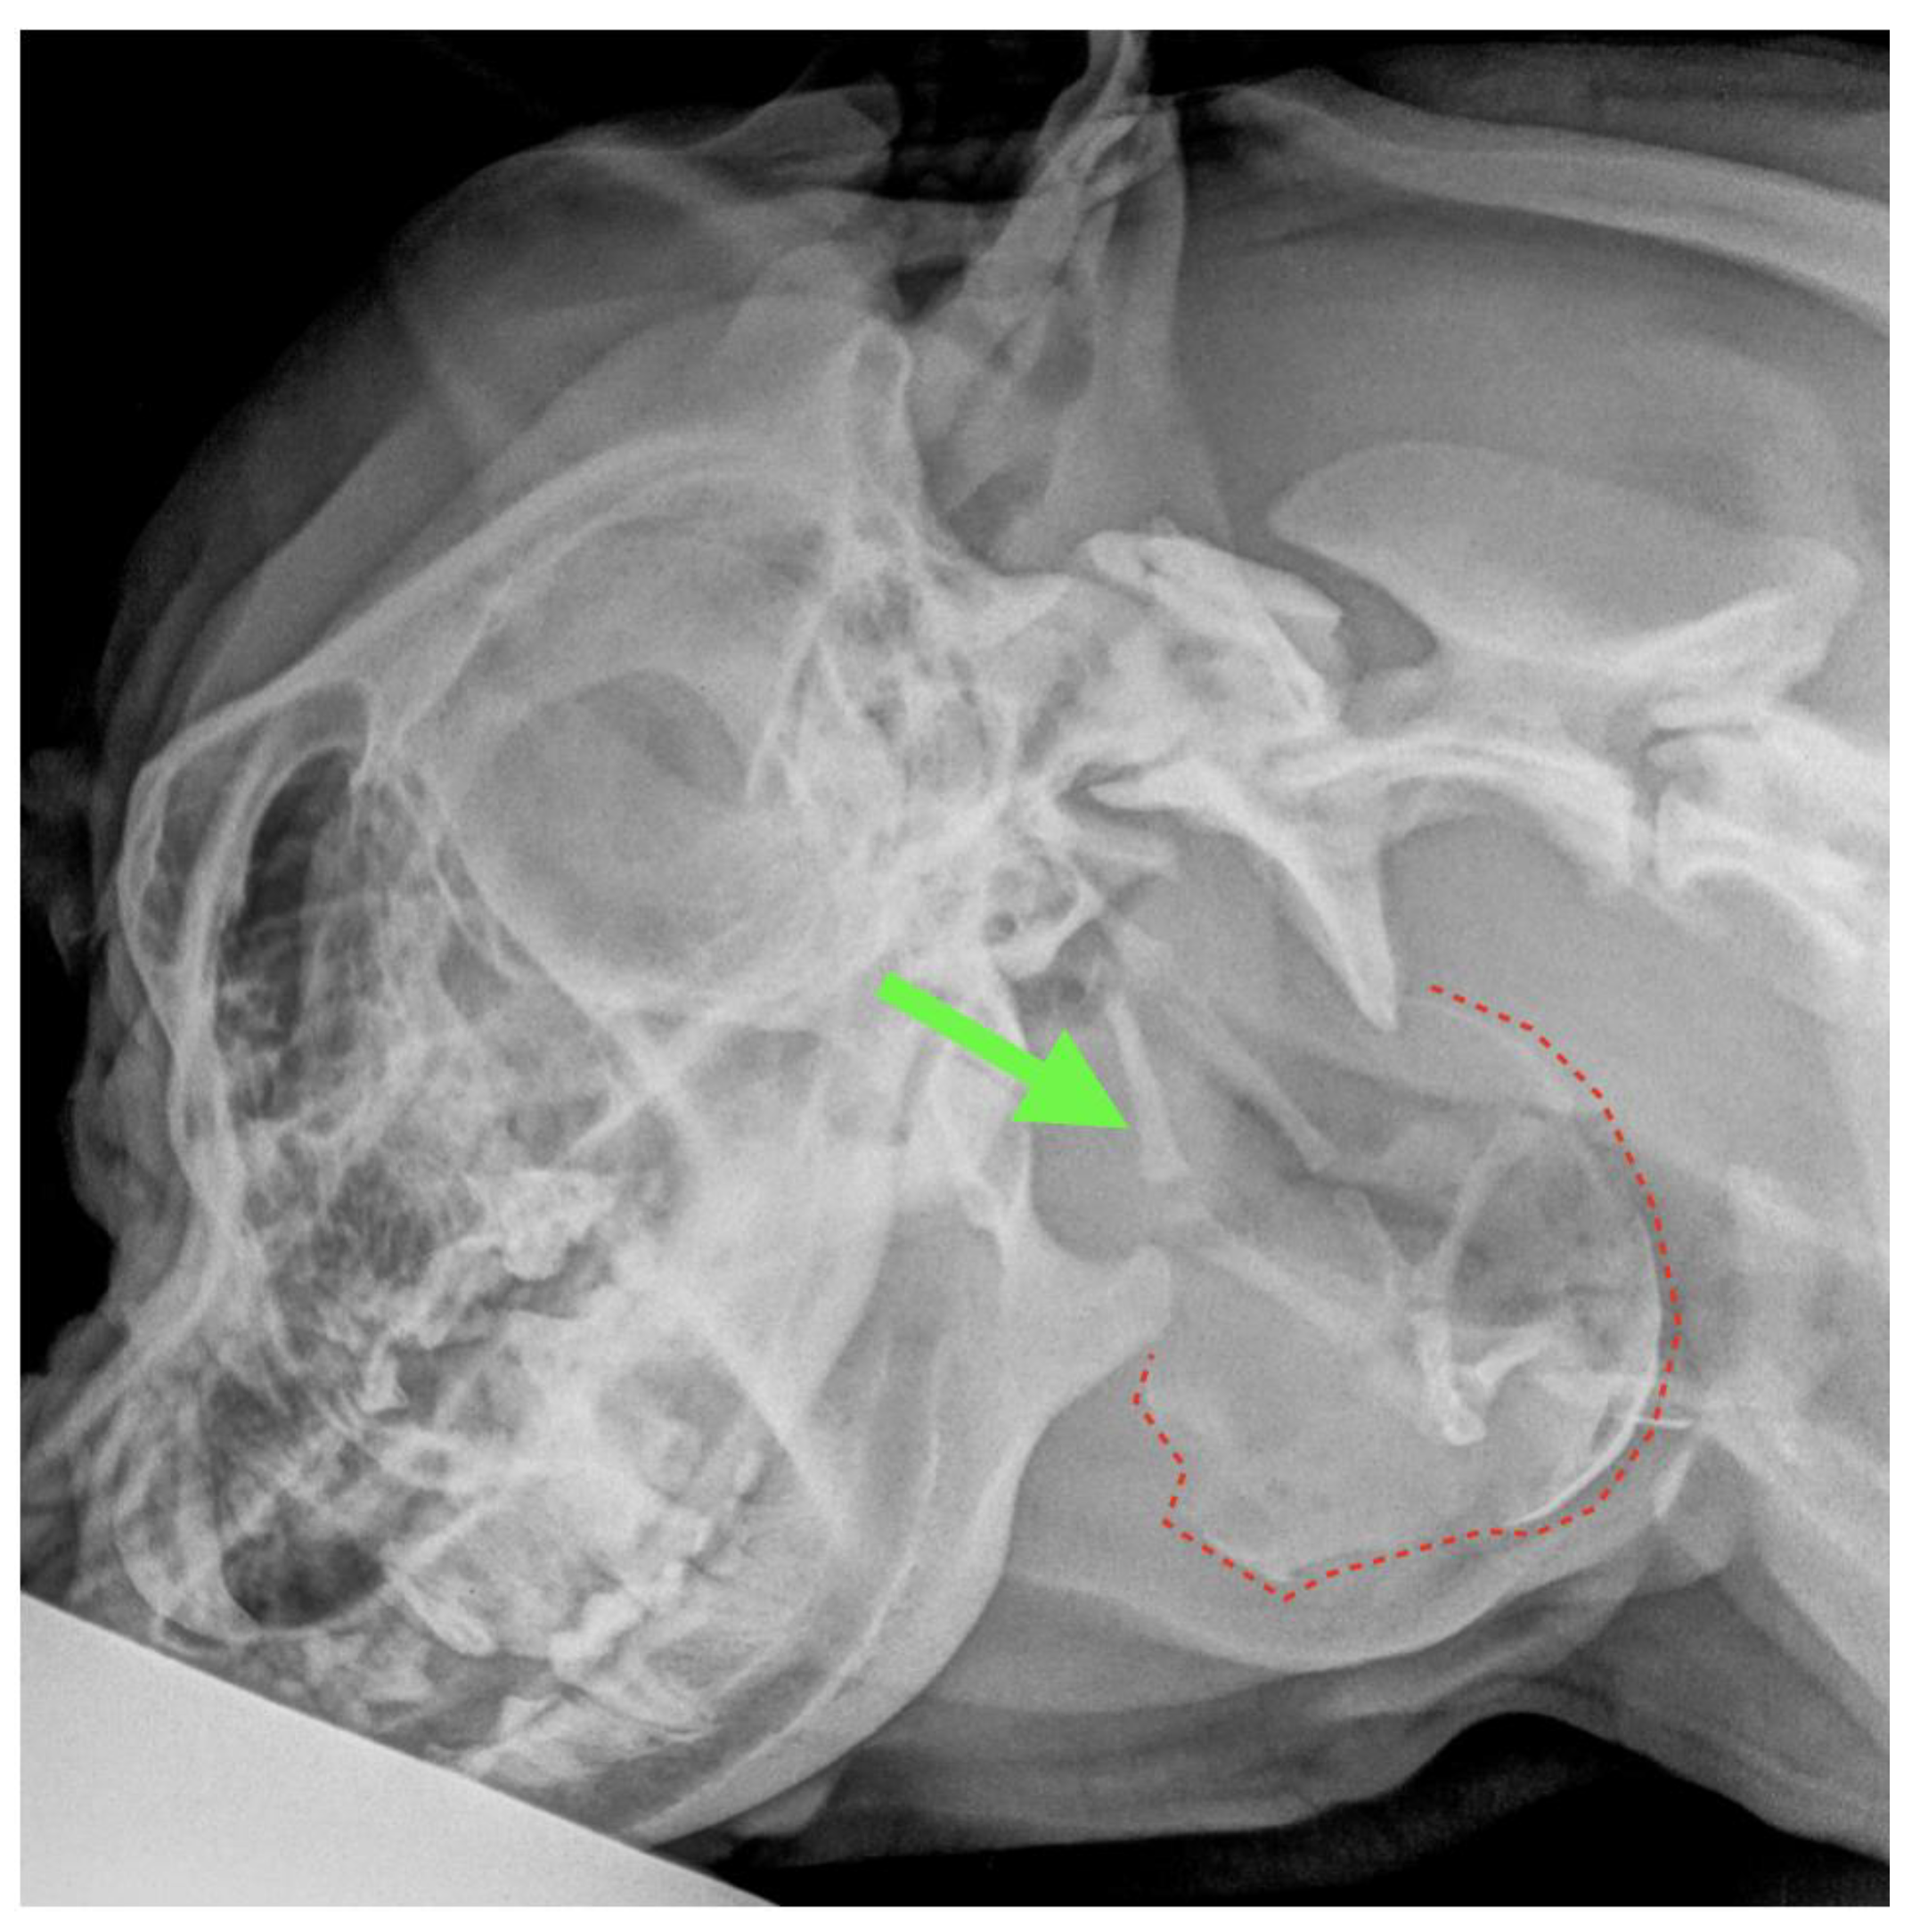

the recommended treatment for a salivary mucocele in dogs involves surgical excision to ensure removal of the affected salivary gland or glands (sialoadenectomy). a salivary mucocele is an accumulation of saliva that has leaked from an injured salivary gland or duct. Some mucoceles cause swelling of the face and neck,. combat stubborn dog saliva stains with proven tips. the removal of salivary glands and ducts through sialocele surgery is a choice. top 5 natural remedies for removing saliva stains from dog fur. Discover practical ways to prevent and remove these. How to remove saliva stains from dog fur using household. Depending on which gland is affected and the surgical site involved, you may be referred to a specialist for this highly technical surgical removal. removal of the salivary glands requires careful dissection to the area of several critically important nerves.

Animals Free FullText Diagnostic Findings and Surgical Management